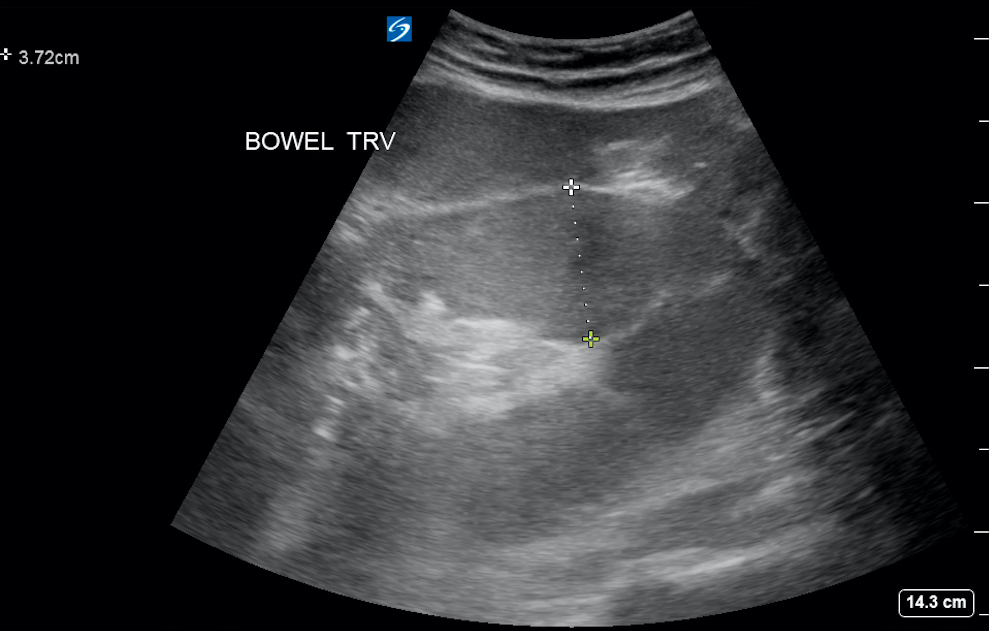

- Figure 2. Dilated small bowel in setting of SBO